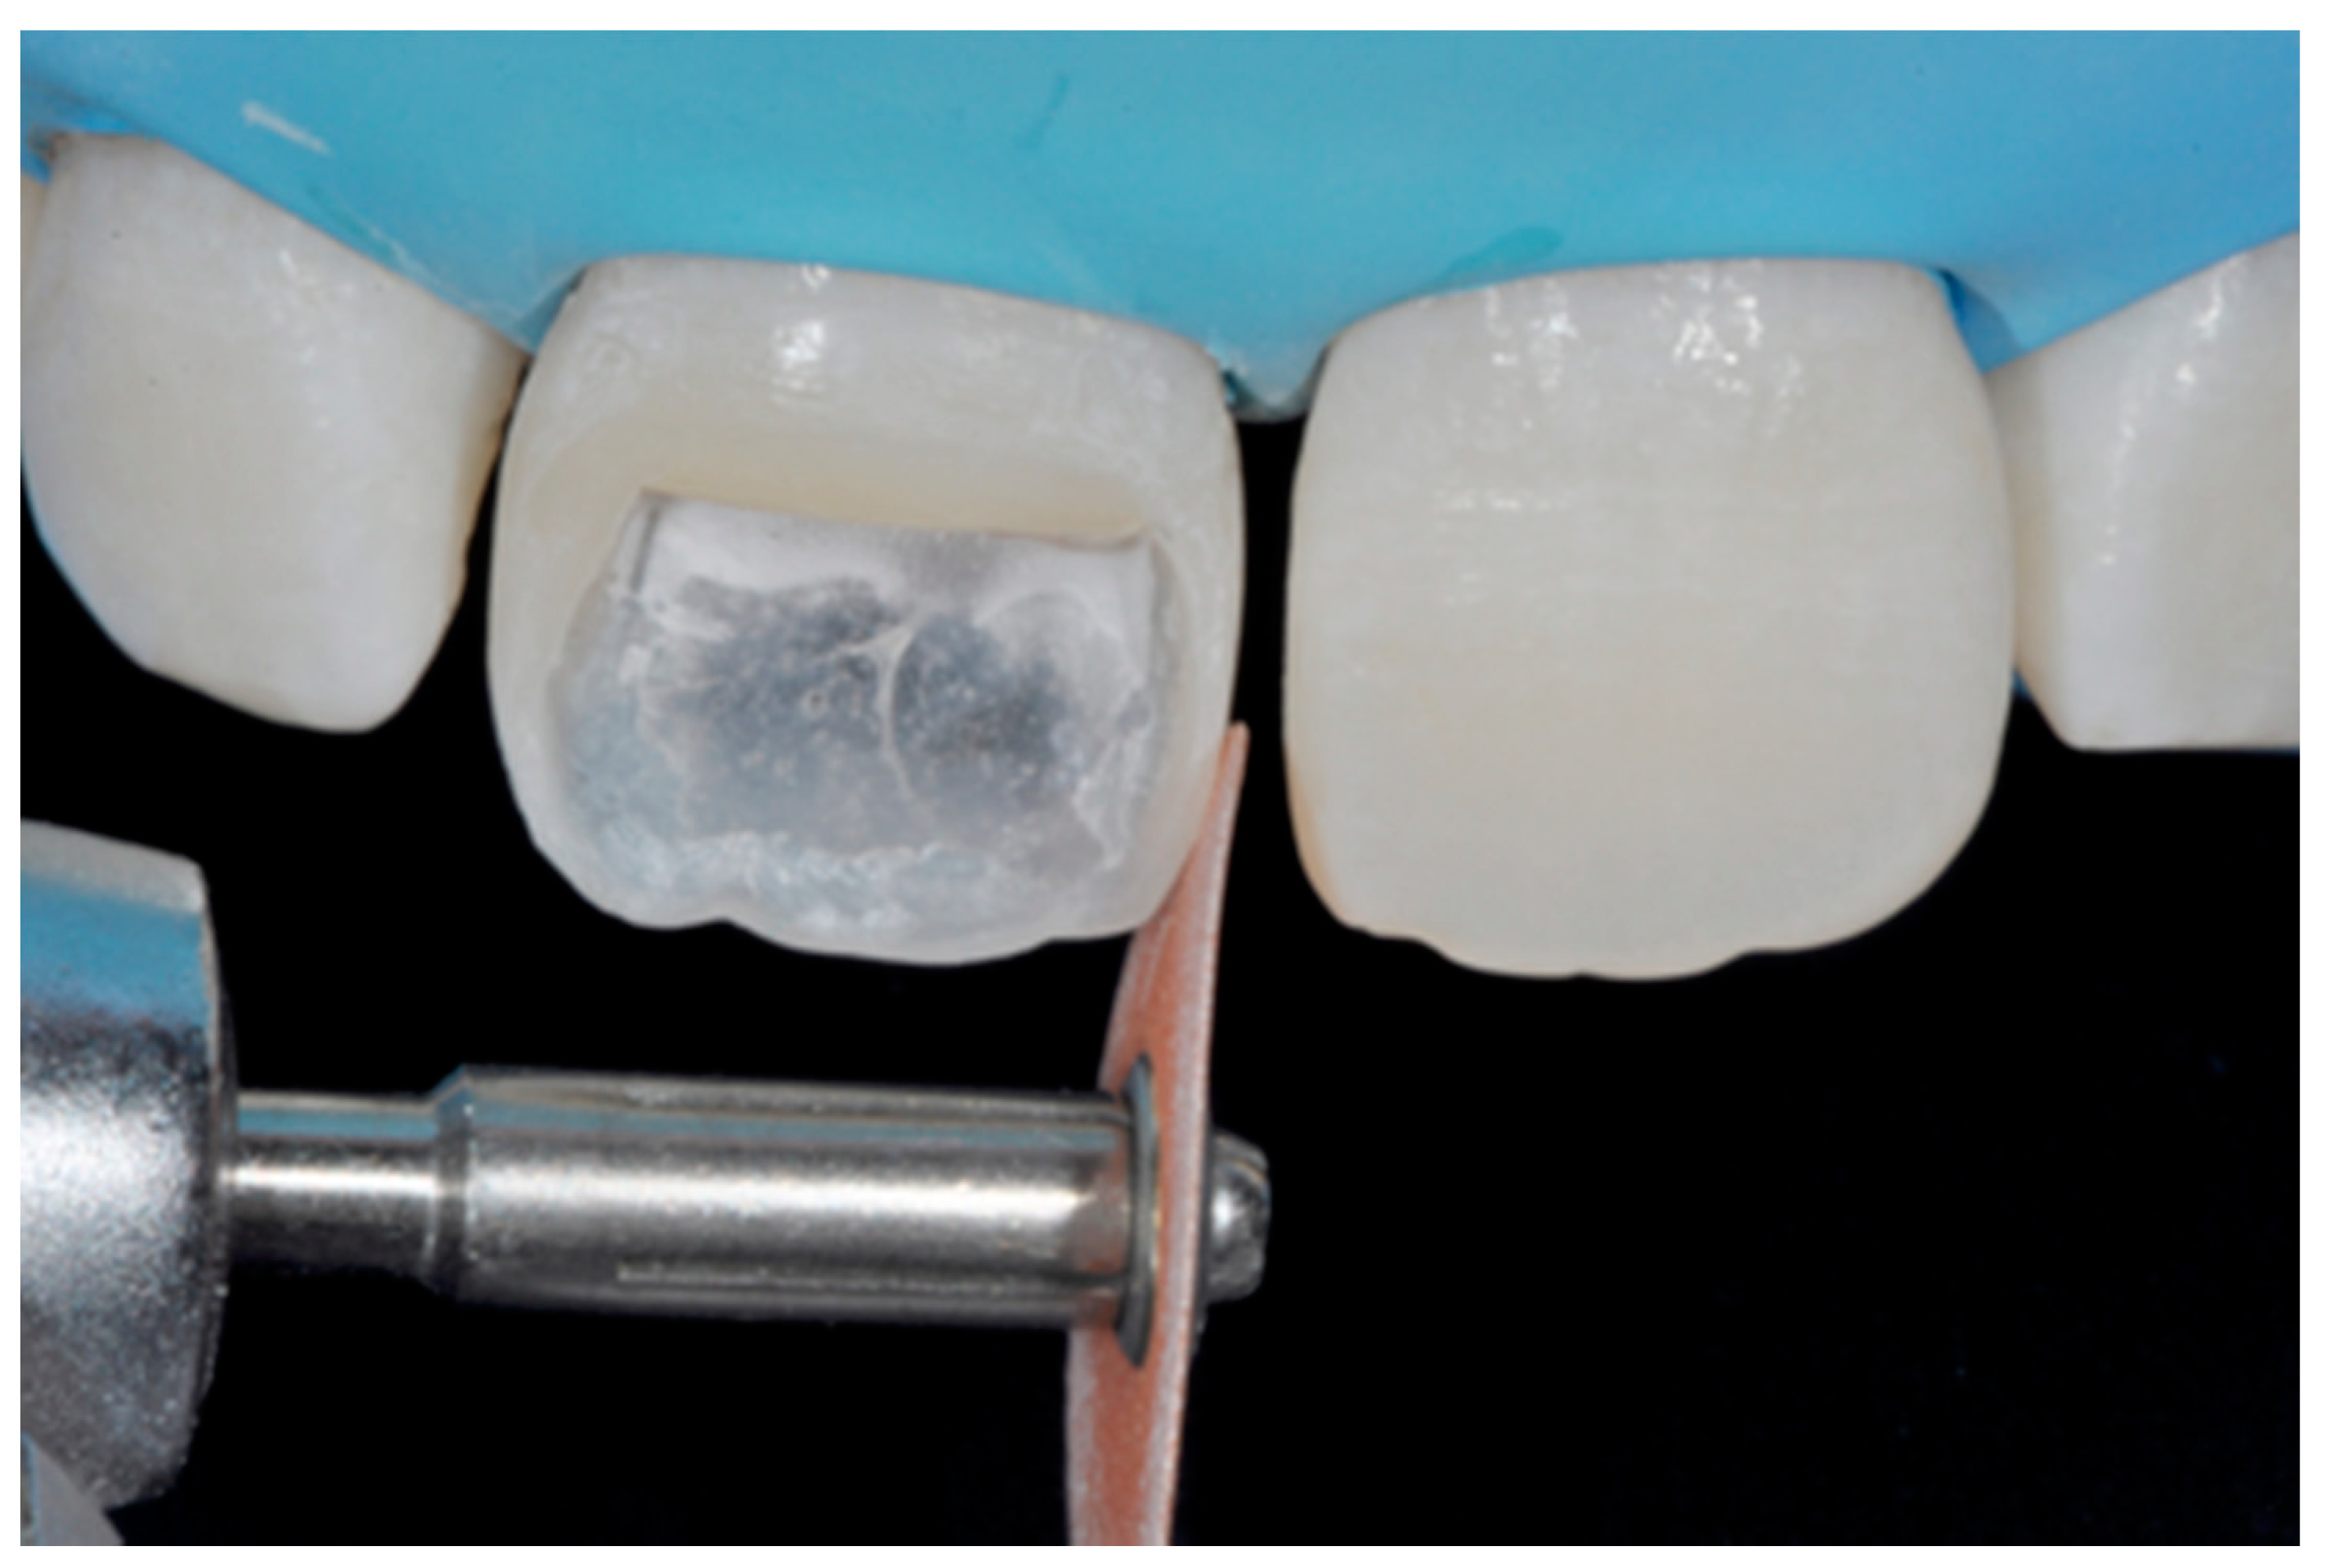

Excesses were removed from the frame (Figure 53) and silane and adhesive were applied following the step-by-step procedure described in Section 2.1.2. Dentinal body (Ceram.x Spectra Effects D1, Dentsply Sirona, York, PA, USA) (Figure 54) was applied to reproduce internal anatomy and then the external translucent enamel and body (Ceram.x Spectra Effects E1, A1, Dentsply Sirona, York, PA, USA) were applied checking precisely thickness and removing excesses with a caliper (Figure 55 and Figure 56) (TNCALIBRA, HuFriedy, Chicago, IL, USA). The restoration shows good integration one-year post-operative (Figure 57).

Figure 55.

Checking and modeling external translucent shade with specific caliper.